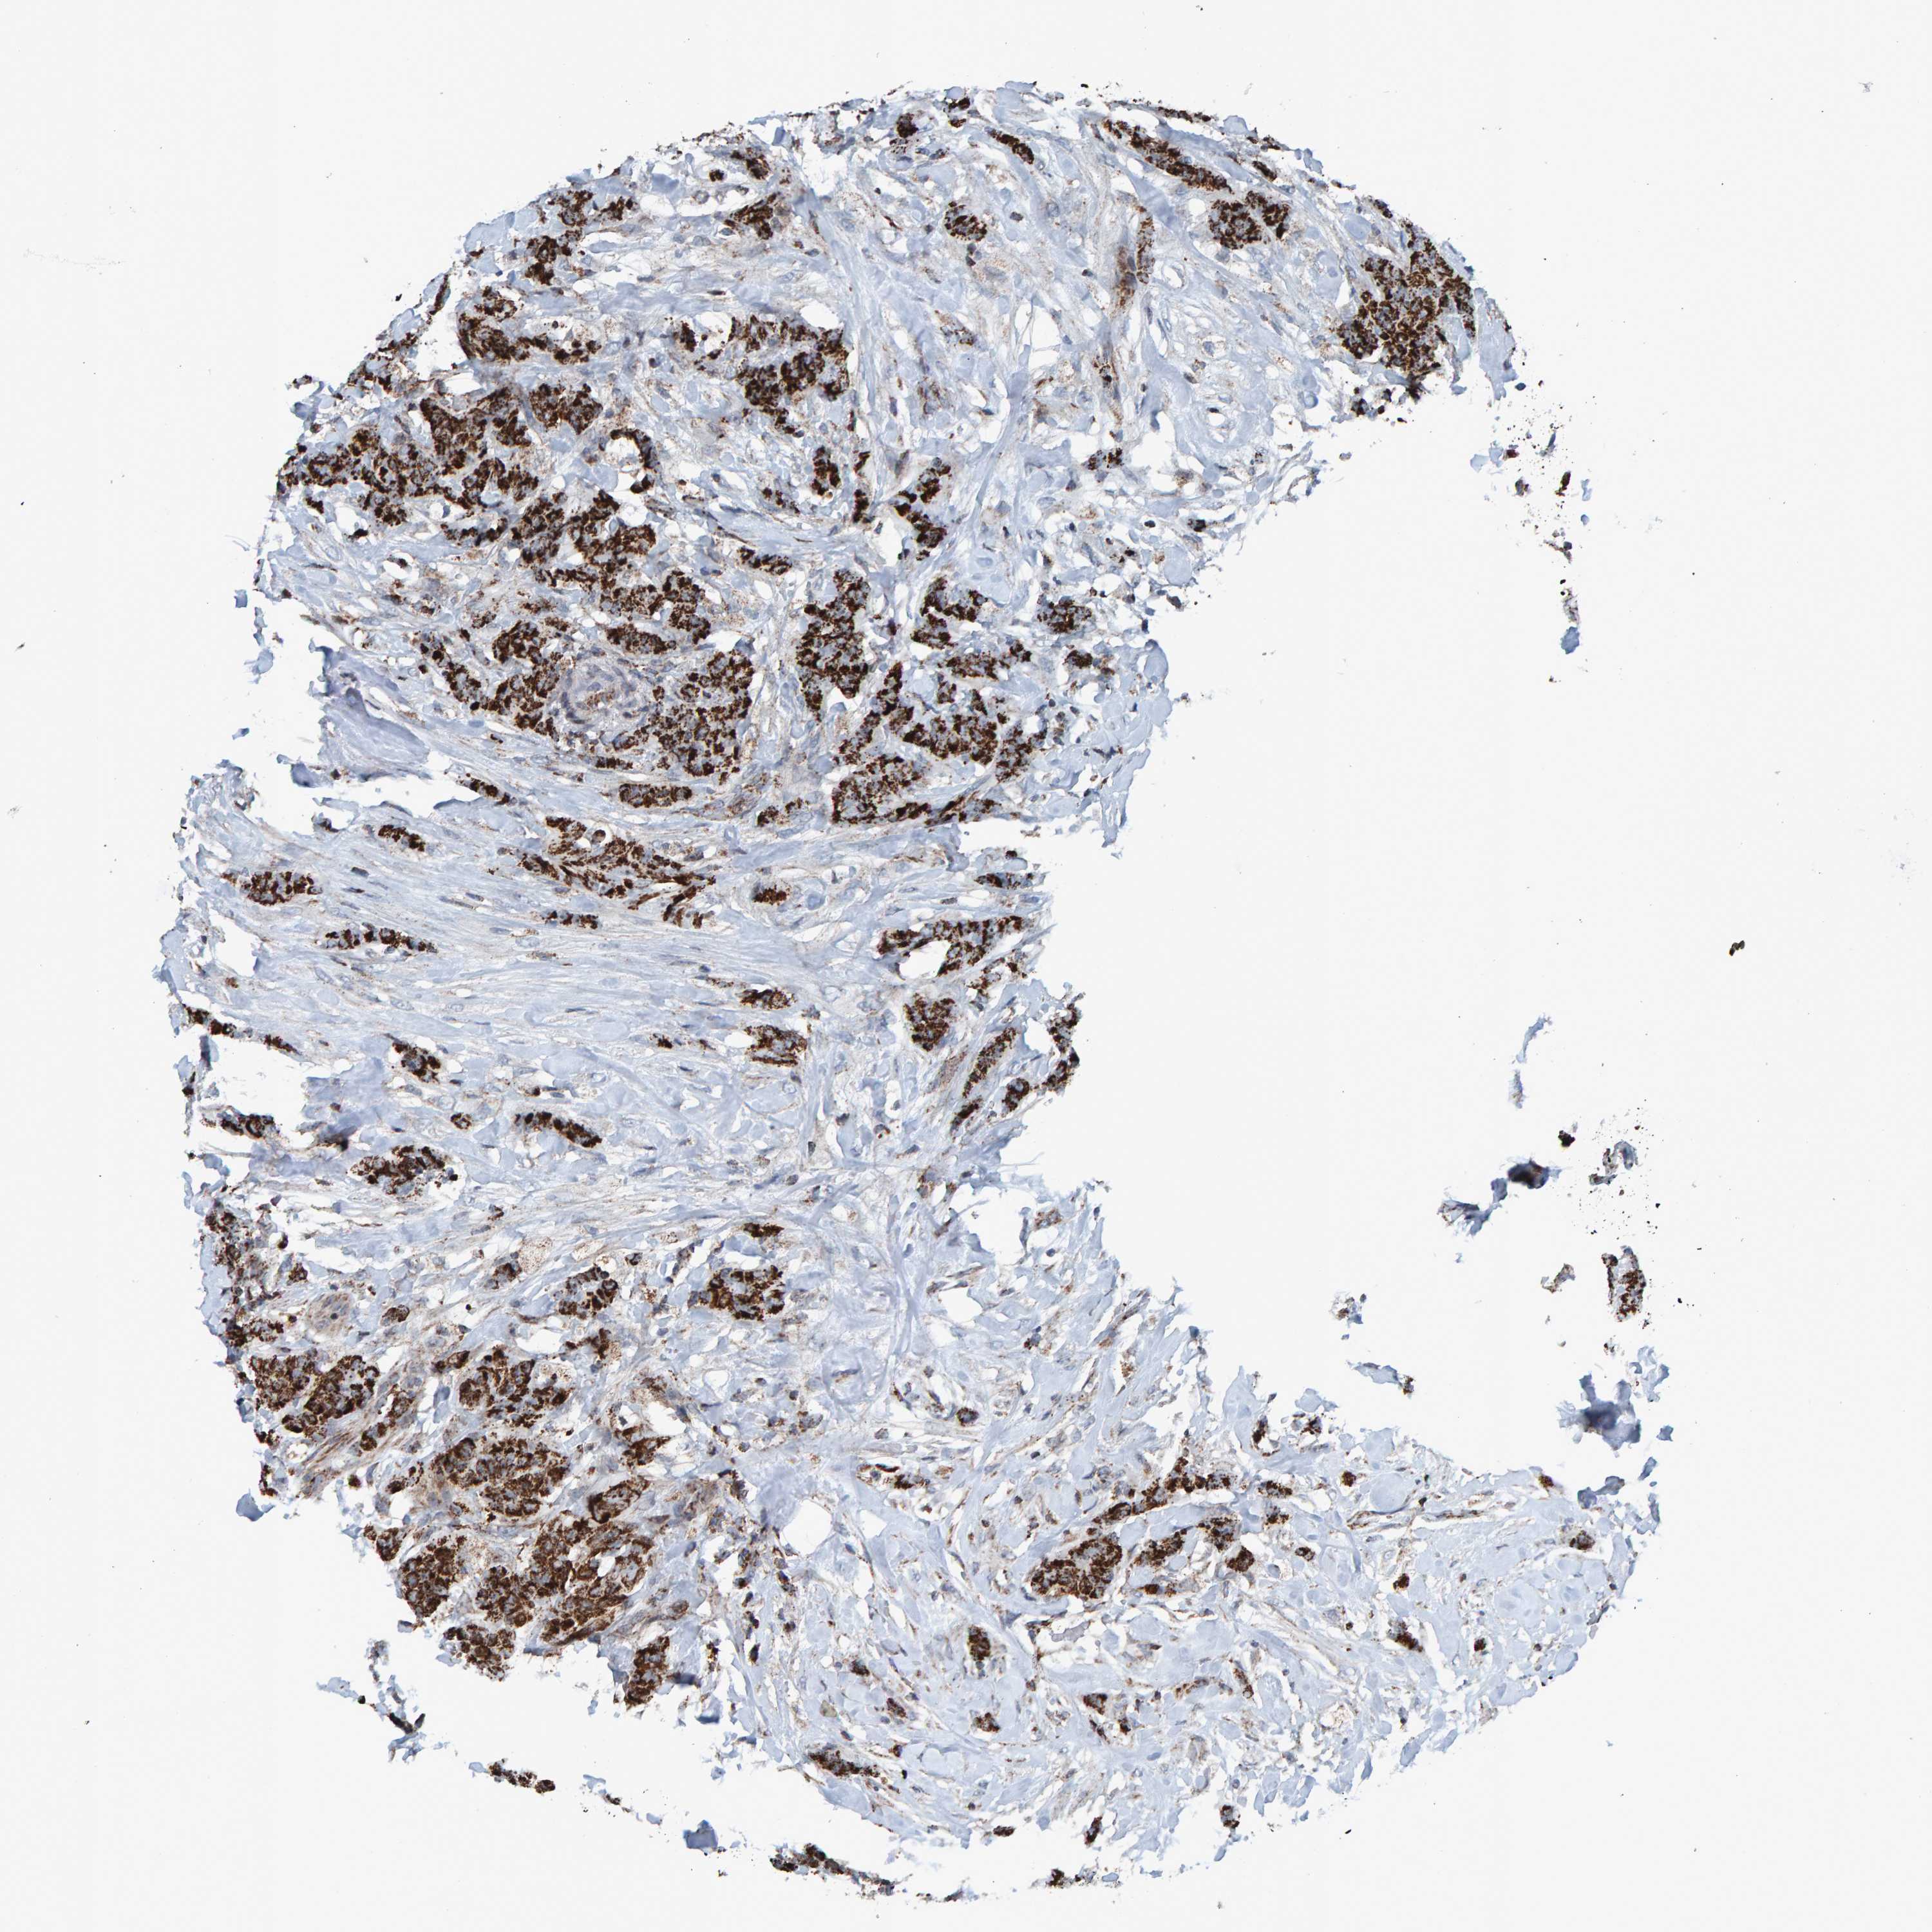

CANCER BREAST CANCER Show tissue menu

BRCA TCGA BRCA VALIDATION PROTEIN EXPRESSION

Breast cancer

Human cancer